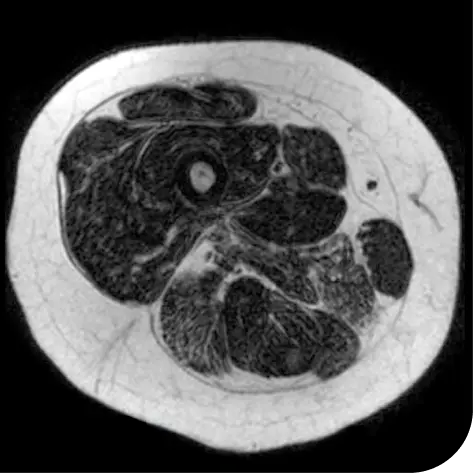

In another follow-up analysis of the clinical trial (meaning it was not one of the main measures planned when the study began), researchers looked at individual people to see how much new fat was in the muscle. The images below represent results from 2 individual people from the study after 18 months. These results may not be the same for everyone.

How to read these images:

- Magnetic resonance spectroscopy (MRS) images can show the difference between muscle and fat in the body

- By taking images of the same patients 18 months apart, researchers can track the amount of new fat that is building up in the muscles

- The darker areas of the images represent muscle tissue and the white areas represent fat

| At the beginning of the clinical trial |

After 18 months | |

Participant taking steroids alone |